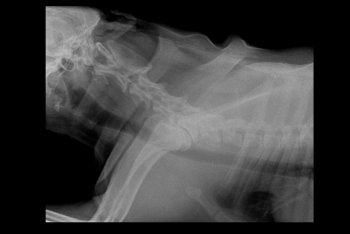

Garret Posted March 14, 2019 Share Posted March 14, 2019 Hi Guys, My dog has been diagnosed with IVDD since February 2nd of 2019. Im at a lost to treat him, please help. So far Im taking him for acupuncture 2x a week. He is being medicated with Analsik 2x a day, and I apply Glucosamine Gel over his joints. Since he has a hard time walking I'm trying to learn to express bladder him, but pooping is still something I can't figure out how to help him does it. So far my vet has diagnosed him with IVDD from looking at his Xray. But there is something that me and my doctor are not sure about which is the Xray on his neck, regarding what is near the AXIS of his neck. I don't know where to ask to next.. I have consulted with 5 vets and not one of them seems to be able to give a definite answer. Some say its a piece of the fracture that broke off, other speculate that it might be cancer. I'm really scared for my dog, and if anyone could help tell me more on what exactly is happening to my dog's neck. or at least point me where I could better ask these questions would help a lot! Link to comment Share on other sites More sharing options...